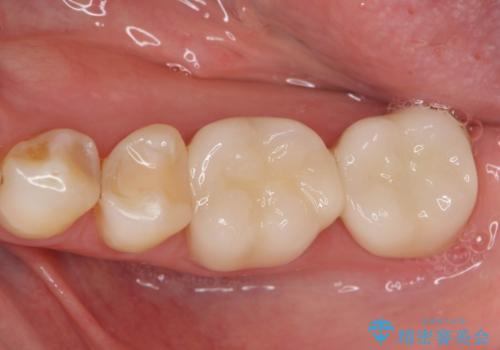

銀歯をセラミック治療で白く

- 「長年使っている奥歯の目立つ銀歯を白くしたい。」、と希望され来院されました。

銀歯を丁寧に除去し、このように銀の覆っている面積が多い場合は、インレータイプではなくより強度に優れ歯もセラミックも長持ちするジルコニアクラウンでの治療を計画します。

天然歯のような白さのセラミッククラウンで、歯本来の審美性を回復することができました。